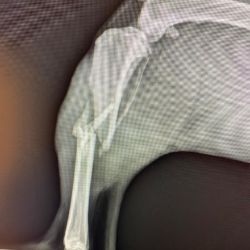

Chirurgie orthopédique et traumatologique

Chirurgie du genou, TPLO